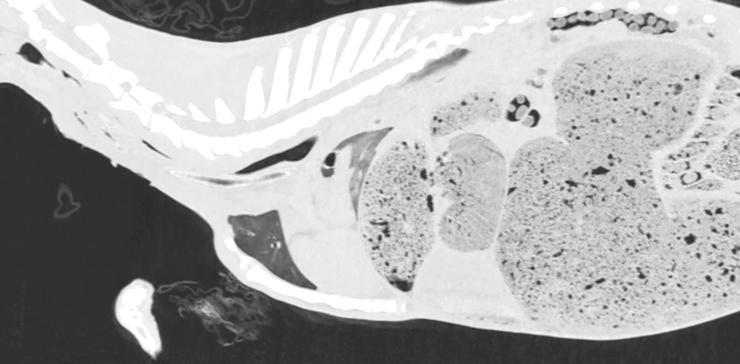

Evaluation of the usefulness of air as a negative contrast medium of blood vessels in goats in post mortem computed tomography (PMCT) and establishing the protocol with appropriate doses and timing of the contrast medium administration.

Thirty three goats were euthanized 10 to 300 min before the study. First, in 3 goats air was administered into the left or right common carotid artery at dose of 60, 100 and 120 ml/kg, and after each dose PMCT was performed in lateral recumbency. As the latter dose proved to visualize blood vessels best, following 30 goats were examined in the same manner but only with the use of air dose of 120 ml/kg. The quality of CT scans was evaluated independently by two board-certified radiologists.

RESULTS

In all studied animals the vascular system filled with air was clearly visualized on CT scans. In most of goats this amount of air revealed vessels smaller than 4 mm in diameter.

评估空气作为死后计算机断层扫描(PMCT)中血管负性对比介质的用途,并制定合适剂量和对比介质给药时间的方案。

33 只山羊在研究前 10 至 300 分钟被安乐死。首先,在 3 只山羊中,以 60、100 和 120 ml/kg 的剂量将空气注入左或右颈总动脉,每次给药后在侧卧位进行 PMCT。由于后一个剂量证明可以最好地显示血管,随后对 30 只山羊以相同的方式进行检查,但仅使用 120 ml/kg 的空气剂量。两名经过委员会认证的放射科医生独立评估 CT 扫描的质量。

结果

在所有研究动物中,血管系统都在 CT 扫描中清晰可见。在大多数山羊中,这种数量的空气揭示了直径小于 4 毫米的血管。